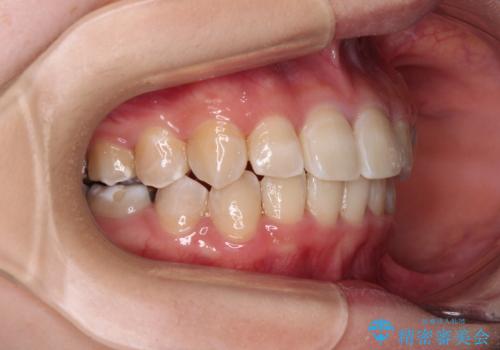

- クリアブラケット

- 犬歯のクロスバイトを気にして来院された患者様です。

マウスピース矯正とワイヤー矯正の両方を提案しましたが、インビザラインの自己管理が煩わしいとのことで、ワイヤー装置による矯正治療を行うこととしました。

犬歯は歯根が太くて長いため、クロスバイトを改善するのは大変であることが多いですが、比較的スムーズに改善することができました。

インビザラインであったら、もっと期間はかかっていたような印象です。